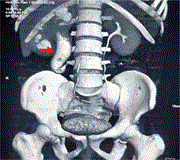

An unusual case of an extensive post-injection retroperitoneal abscess in an intravenous drug user

Georgios Gerasopoulos and others

Journal of Surgical Case Reports, Volume 2024, Issue 6, June 2024, rjae398, https://doi.org/10.1093/jscr/rjae398